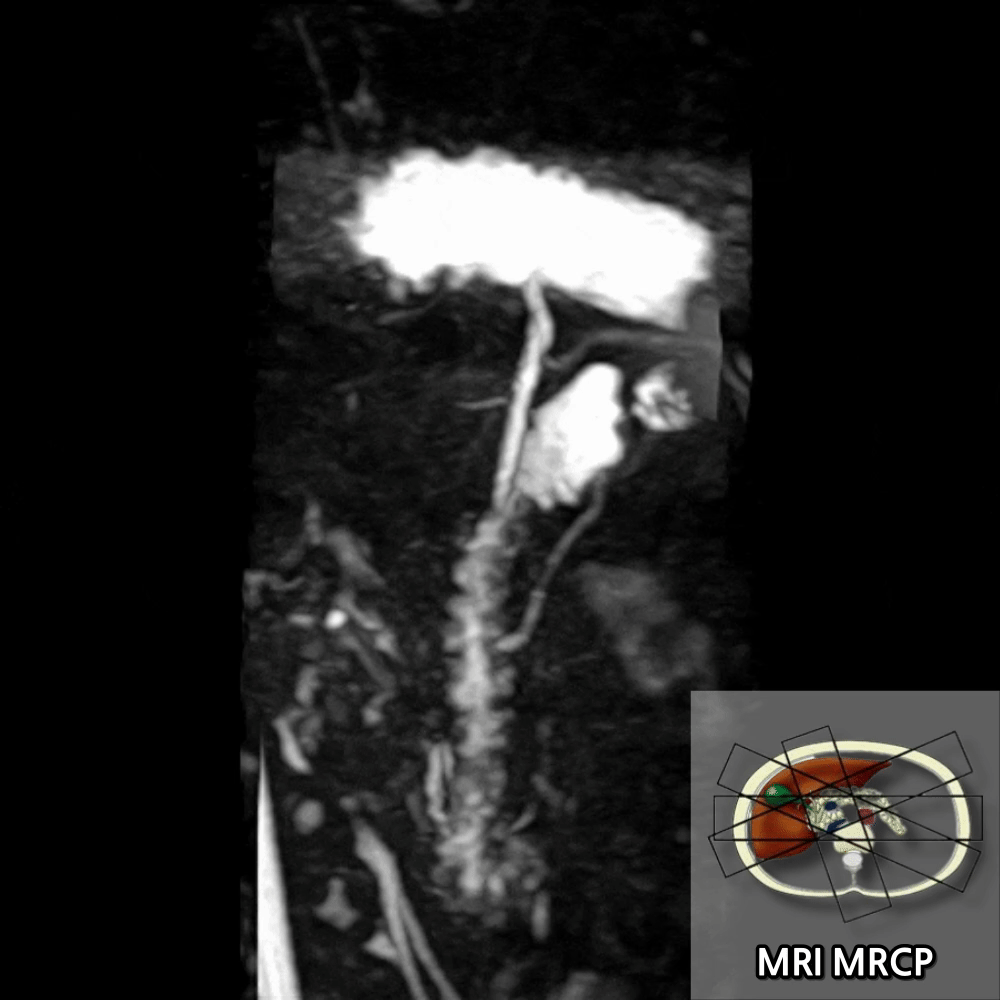

– MRCP는 고T2강조로 췌관·담관 내 액체를 밝게 표현하여 관 구조를 가시화

췌장 MRI는 췌장 실질(염증·종양·낭종)을, MRCP는 담도·췌관 모양을 물처럼 보여주는 특수 기법으로 결석·협착 평가에 유용합니다.